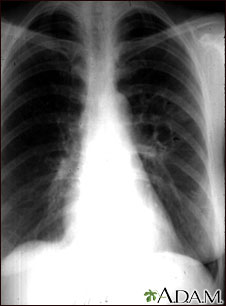

This chest x-ray shows the affects of a fungal infection, coccidioidomycosis. In the middle of the left lung (seen on the right side of the picture) there are multiple, thin-walled cavities (seen as light areas) with a diameter of 2 to 4 centimeters. To the side of these light areas are patchy light areas with irregular and poorly defined borders.

Other diseases that may explain these x-ray findings include lung abscesses, chronic pulmonary tuberculosis, chronic pulmonary histoplasmosis, and others.